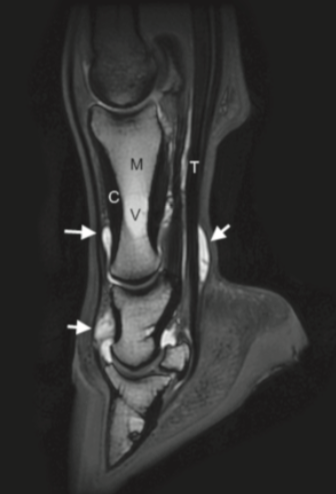

Appearance of fat and fluid on T2-weighted images

On T2 - 2 things are white; fat and water

Trabecular bone and synovial fluid are both hyperintense. The easiest way to distinguish T1 and T2 images is to observe the signal intensity of fluid.

How to differentiate fluid from sclerosis

Need to look at multiple sequences

Fluid and sclerosis are indistinguishable on T1-weighted images. However fluid will have intermediate-high signal intensity on T2, STIR and PD images

PD and T2-weighted FSE sequences provide a definitive way to identify sclerosis, when compared with the T2* gradient-echo images as there is no overlap between the appearance of fluid and sclerosis on these sequences